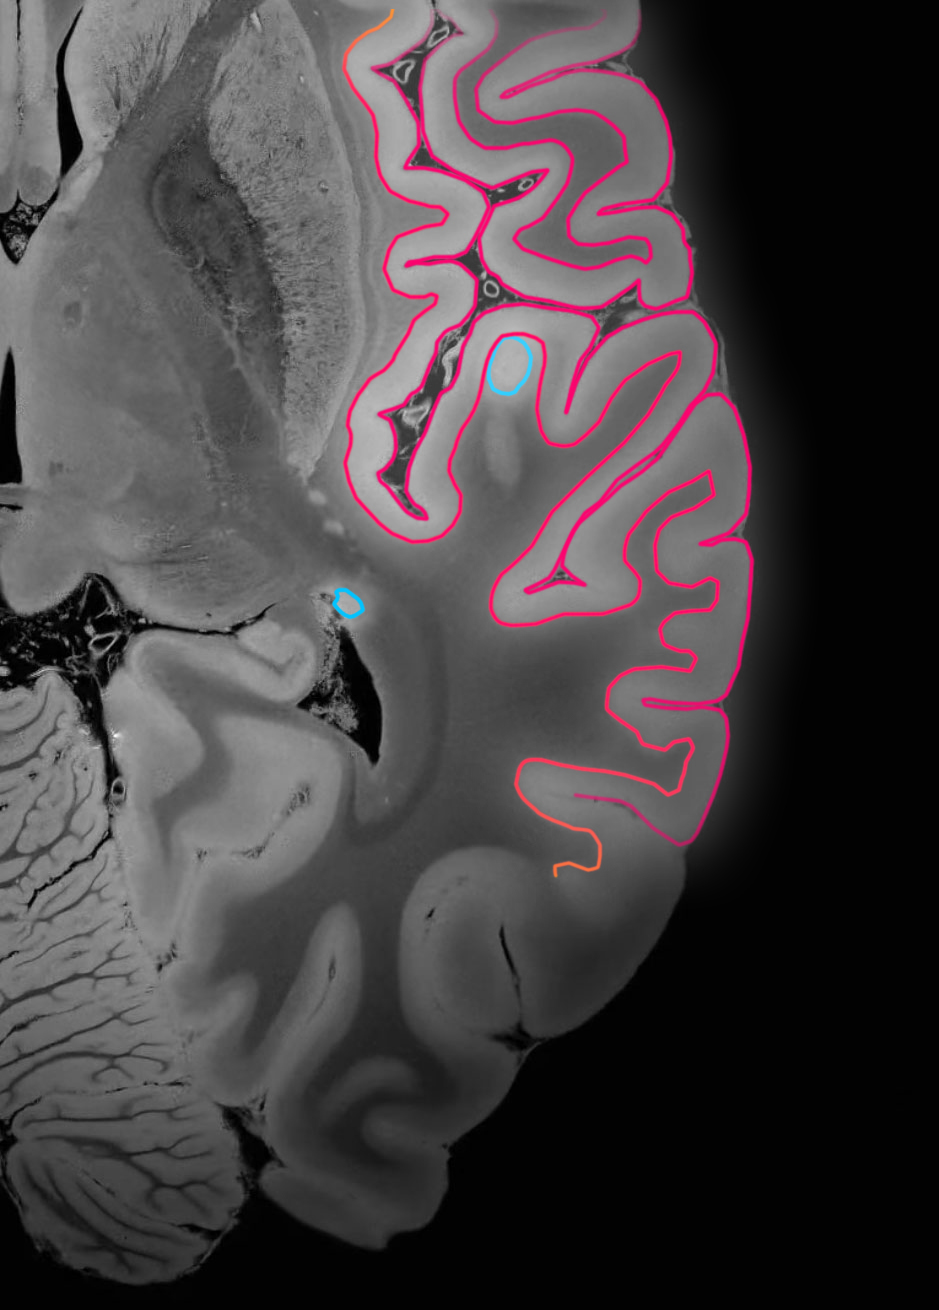

We offer artificial intelligence (AI) solutions for advanced assessment and analysis of brain MRI studies.

We develop innovative solutions based on artificial intelligence (AI) for advanced assessment and analysis of brain MRI studies. This is our response to the growing demand for effective tools supporting the diagnosis and monitoring of the course of neurodegenerative and demyelinating diseases.